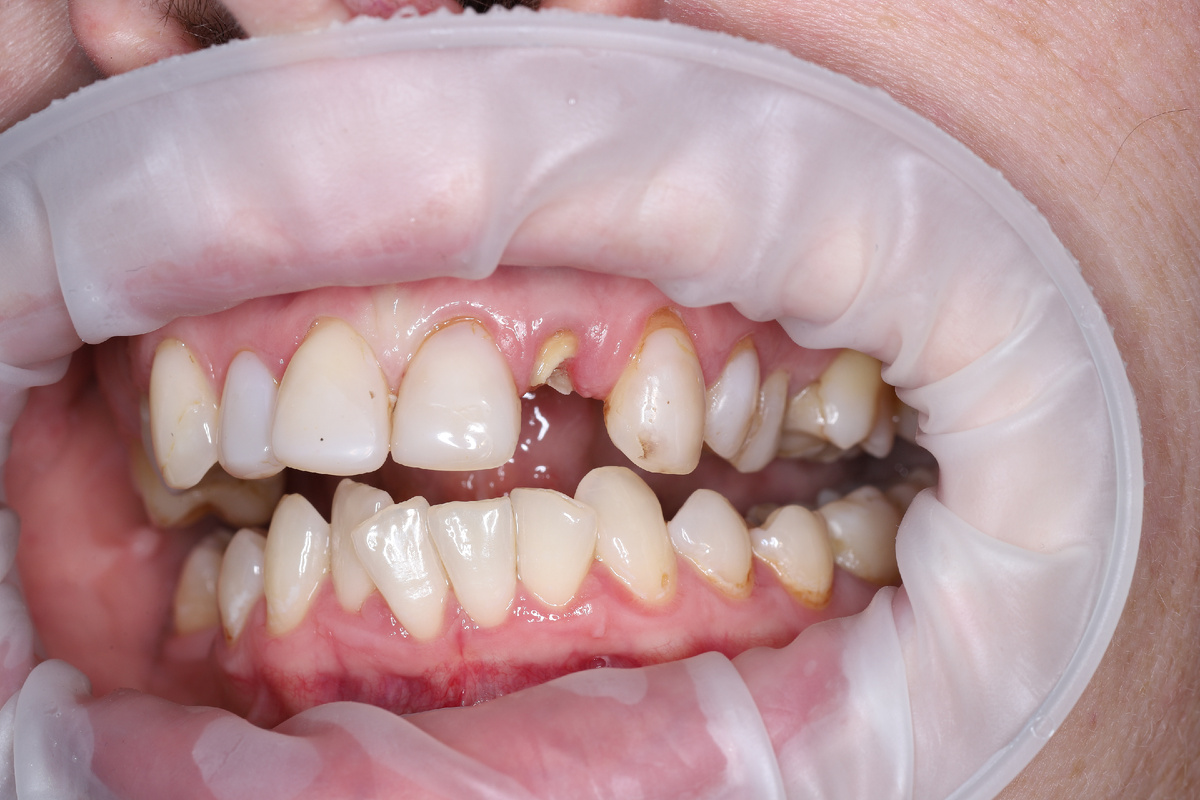

Через 3 месяца заменили временную коронку постоянной:

После фиксации постоянной коронки

Пациент остался очень доволен, проведенной работой. А я рад, что смог помочь.

В свою очередь добавлю, что мы сохранили природоподобный контур десны, зубодесневые сосочки, а сам зуб получился очень красивым и функциональным.